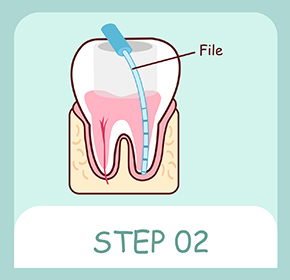

ファイルと呼ばれる器具でむし歯菌によって感染した神経や血管を取り除き、根管長測定器で根の長さを測ります。